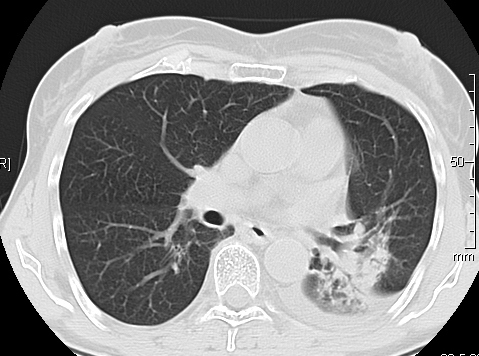

Foto: Aleksandar Ivković Foto: Aleksandar Ivković Foto: Aleksandar Ivković Strašna razlika kod pluća pušača i kovid pozitivne osobe autor: Božica Luković Zdravlje 23. jan. 2021. 12:06 > 23. jan. 2021. 12:15 0 Podeli vest: Radiolog Aleksandar Ivković od početka pandemije daje korisne informacije o svim aspektima kovida 19. On je nedavno uporedio rendgen snimke pluća zdrave osobe, pušača, osobe koja je zaražena gripom H1N1, a onda i osobe koja ima kovid 19. Razlike su zapanjujuće. Podeli vest: Oglas Objavu doktora Ivkovića sa njegovog bloga "Ljudi i ostale laži" prenosimo u celosti."Nedavno sam video u medijima da je neko preneo rdg sliku i razlike kod nalaza zdrave osobe, pušača i bolesnog od kovida 19. Kako nisam baš previše zadovoljan onim što je prikazano, evo kako to izgleda u našoj varijanti. Zdrava osoba CT nalaz kod zdrave osobe podrazumeva da ne postoje nikakvi poremećaji strukture plućnog parenhima, da su krvni sudovi uredni i da nema suženja disajnih puteva, kao i da nema uvećanih limfnih žlezda u hilusima pluća i medijastinumu. Foto: Aleksandar Ivković | Foto: Aleksandar Ivković * Foto: Aleksandar Ivković | Foto: Aleksandar Ivković Zdrava muška osoba mesec dana nakon zapaljenja pluća tokom kovida 19. Nalaz bez nekih posebnih problema iako se naziru tragovi zapaljenja. Snimak u boji je zdrava osoba, nepušač, bez ikakvih bolesti pluća u istoriji. Grip H1N1 Pokazaću samo drastične nalaze kod gripa H1N1, to je znači onaj grip koji je izazvao epidemiju španske groznice i epidemiju 2009. godine koja još uvek nije prestala (svake godine imamo makar 15%). Foto: Aleksandar Ivković | Foto: Aleksandar Ivković * Foto: Aleksandar Ivković | Foto: Aleksandar Ivković * Foto: Aleksandar Ivković | Foto: Aleksandar Ivković * Foto: Aleksandar Ivković | Foto: Aleksandar Ivković Nisu svi pacijenti imali ovakve nalaze, pokazujem one koji su imali tešku kliničku sliku. Kod gripa se sve odvija obično u sedam dana. Kao što se vidi, zapaljenje je bilo jednostrano, uglavnom. Ali kada je dolazilo do pogoršanja, onda je centralno obostrano dolazilo do edema pluća. Pušenje Kod pušača postoje razne varijante nalaza na plućima. U principu nisu tako dramatične kao što su zapaljenja. Nalaz na plućima kod pušača može biti potpuno normalan. Ovo ne pišem zato što podržavam pušenje, naprotiv, veliki sam protivnik, ali iznošenje laži nikada nije dobro. Dve dijagnoze su bitne kao posledica pušenja. Prva je hronična plućna opstruktivna bolest: Foto: Aleksandar Ivković | Foto: Aleksandar Ivković * Foto: Aleksandar Ivković | Foto: Aleksandar Ivković * Foto: Aleksandar Ivković | Foto: Aleksandar Ivković Jasna je razlika u nalazu, posebno na ovim slikama u boji, gde su ta plava polja delovi pluća koji su propali zbog cigareta (može da se uporedi sa zdravim plućima iznad).Druga bolest koja je česta kod pušača je u svakom slučaju karcinom. Foto: Aleksandar Ivković | Foto: Aleksandar Ivković * Foto: Aleksandar Ivković | Foto: Aleksandar Ivković * Foto: Aleksandar Ivković | Foto: Aleksandar Ivković * Foto: Aleksandar Ivković | Foto: Aleksandar Ivković Tkivo koje raste unutar pluća i razjeda ga. Takav je nalaz kod karcinoma pluća. Često je uzrok upotreba cigareta. Kovid 19 O kovidu sam pisao puno puta. Evo nekih slika, radi poređenja. Foto: Aleksandar Ivković | Foto: Aleksandar Ivković * Foto: Aleksandar Ivković | Foto: Aleksandar Ivković * Foto: Aleksandar Ivković | Foto: Aleksandar Ivković * Foto: Aleksandar Ivković | Foto: Aleksandar Ivković Nakon što pacijent bude izlečen od gripa ili kovida 19, pluća se mogu vratiti u normalu.To je razlika u odnosu na posledice upotrebe cigareta. Ovi snimci nisu postavljeni da bi se poredile bolesti, već da bi se ukazalo kako različite bolesti deluju na pluća. I ono što je veoma važno, ako neko dobije jednu od ovih bolesti, ne znači da u toku života neće dobiti drugu.Ne pišem zato smo smatram da sam najpametniji ili najpozvaniji da objašnjavam, nisam kao neki pojedinci ubeđen da samo ja imam znanje i istinu, pišem jer drugi ćute. Pišem jer ima i puno onih koji iznose laži, mora se tome stati na put.A ovi, koji pišu da sam umro, da sam oboleo od karcinoma, ovi koji mi žele da nađem dobro grobno mesto, šta da vam kažem, vi ste mi inspiracija. Svesni ste da sam u pravu i odlično znam da ste već uradili sve da se vakcinišete i mnogi od vas će to uraditi pre mene ali i dalje ćete ubeđivati druge da se ne vakcinišu i da je dobro za njih da se razbole i umru. Ima puno reči za vas u svim našim slovenskim jezicima, znate vi sami šta ste", piše dr Ivković.***Bonus video:https://youtu.be/MWucTT0qBsIPratite nas i na društvenim mrežama:FacebookTwitterInstagram Dr Lukić otkrio spisak svih antibiotika za kovid upalu pluća Zdravlje 0 Dr Žujović: Kako oporaviti pluća posle korone Zdravlje 0 Pet znakova da ti je kovid zahvatio pluća Zdravlje 0 Virusolog Ana Banko ruši veliku zabludu o ruskoj vakcini Emisije 0 aleksandar ivković korona kovid pluća snimak pluća Pratite nas na društvenim mrežama: Koje je tvoje mišljenje o ovoj temi? Učestvuj u diskusiji ili pročitaj komentare Budite prvi koji će ostaviti komentar Pošalji komentar Pročitaj komentare (0)